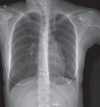

Vanishing lung syndrome

- Roberts L, Putman CE, Chen JTT, Goodman LR, Ravin CE. Vanishing lung syndrome: Upper lobe bullous pneumopathy. Revista interamericana de radiología. 1987;12:249–55.